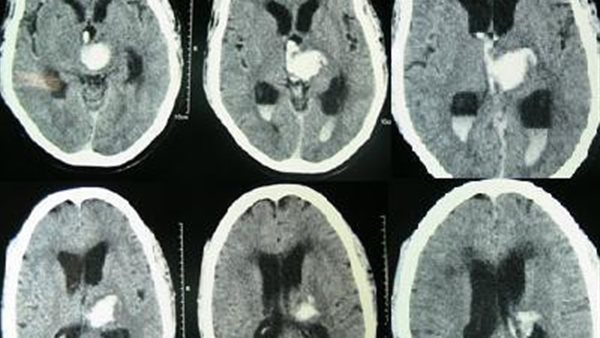

وأضاف جمال، أنهم نقلوا أخاه إلى أحد المستشفيات الخاصة، وأدخله الأطباء إلى العناية المركزة، بعد أن تمكنوا من وقف النزيف، وأجروا الفحوصات اللازمة له لمتابعة وتشخيص الحالة، حيث أجروا بعض الأشعات المقطعية والتحاليل الطبية.

وأشار جمال شقيق إبراهيم، إلى أن الأطباء بعد مراجعة التقارير والتحاليل، أوضحوا أن شقيقه أُصيب بانفجار شريان داخل المخ، والذي يحتاج لعلاجه إلى قسطرة علاجية على الدماغ، وتكلفتها عالية جدًا.